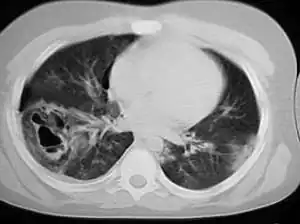

A chest CT scan revealing pulmonary contusions, pneumothorax, and pseudocysts

Pseudocysts are like cysts, but lack epithelial or endothelial cells. Initial management consists of general supportive care. Symptoms and complications caused by pseudocysts require surgery. Computed tomography (CT) scans are used for initial imaging of cysts, and endoscopic ultrasounds are used in differentiating between cysts and pseudocysts. Endoscopic drainage is a popular and effective method of treating pseudocysts.